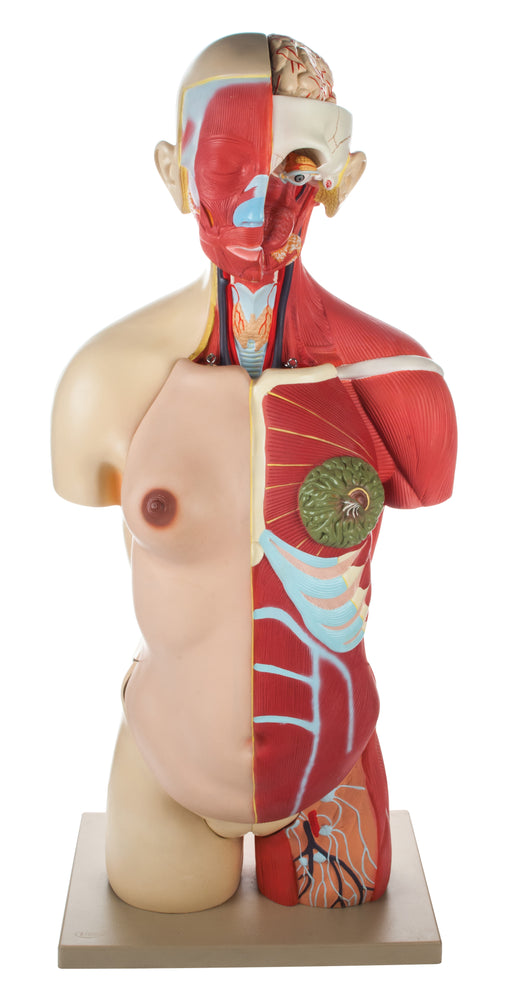

Full Muscle Torso with Dual Sex Organs and Open Back Ÿ?? 24 Parts

The detailed, life size 3D rendering of the human torso with its vibrantly colored anatomy is ideal for studying the structure and function of the ...

View full detailsAM16003 -

Full Muscular Torso Natural with Dual Sex Organs (30 Parts)

The detailed, life size 3D rendering of the human torso with its vibrantly colored anatomy is ideal for studying the structure and function of the ...

View full detailsAM16001 -

Human Half Muscle Female Torso with Dual Sex Ÿ?? Economy Ÿ?? 17 Parts

The detailed, life size 3D rendering of the human torso with its vibrantly colored anatomy is ideal for studying the structure and function of the ...

View full detailsAM16005 -

Half Muscle Torso with Dual Sex Organs 28 Parts

The detailed, life size 3D rendering of the human torso with its vibrantly colored anatomy is ideal for studying the structure and function of th...

View full detailsAM16004 -

Half Size Muscular Torso 24 Parts

The detailed, half size 3D rendering of the human torso with its vibrantly colored anatomy is ideal for studying the structure and function of the ...

View full detailsAM16008 -

Half Muscle Torso with Dual Sex Organs and Open Back - 30 Parts

The detailed, life size 3D rendering of the human torso with its vibrantly colored anatomy is ideal for studying the structure and function of th...

View full detailsAM16002 -

Human Full Muscle Torso with Dual Sex Organs 20 Parts

The detailed, life size 3D rendering of the human torso with its vibrantly colored anatomy is ideal for studying the structure and function of the ...

View full detailsAM16006 -

Model, Human, Open Back Toroso, Dual Sex, 27 Parts

Life size Dual Sex Excellent detail 33 inches tall Life size human torso is an excellent tool for anatomy studies. It features a dissected head t...

View full detailsAM11AAS -